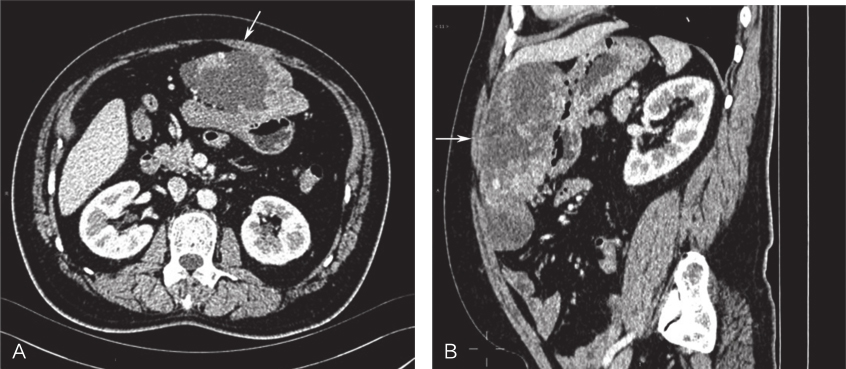

全腹部及盆腔增强CT:①中上腹腔见一大小约12.4cm×5.9cm×16.4cm不规则软组织肿块影,增强扫描呈明显不均匀强化,胃左、胃右动脉及胃网膜右动脉似发出分支供血上述肿块,动脉期肿块内可见迂曲增粗血管显影,并与胃右动脉相连通,胃右静脉增粗,门静脉部分早期显像,提示动静脉瘘,肿块局部与胃大弯侧胃壁及邻近肠管分界欠清,其周围脂肪间隙清晰,未见明显肿大淋巴结,上述多考虑为肿瘤性病变:胃肠间质瘤?②肝脏、胆囊、脾脏、胰腺及双肾未见明显异常密度影;③乙状结肠冗长;④膀胱充盈良好,壁尚光滑;⑤腹腔及腹膜后未见明显肿大淋巴结(图1)。

图1术前全腹部及盆腔增强CT

A.横断位;B.矢状位